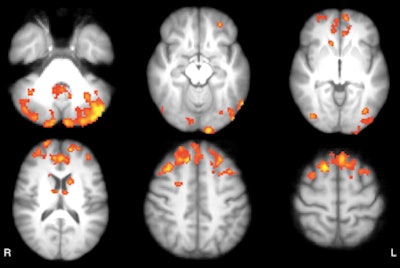

As one might expect, baseline resting-state fMRI showed that MS patients had significantly lower functional connectivity clusters in the cerebellum, frontal and occipital cortices, caudate nucleus, and thalamus than the healthy subjects.

Axial statistical maps show areas of reduced thalamic functional connectivity in patients with MS compared with healthy subjects. Patients exhibited significantly lower functional connectivity in clusters located in the cerebellum, frontal and occipital cortices, caudate nucleus, and thalamus, bilaterally. Image courtesy of Radiology.However, there was no significant difference in baseline functional connectivity maps of the thalamic resting-state network between the waitlist and intervention groups. The scans covered the cerebellum, thalamus, basal ganglia, and cingulate, frontal, temporal, occipital, and bilateral parietal cortices.